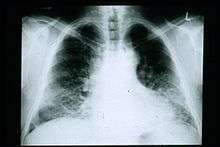

Chest X-rays are useful in the follow up routine of IPF patients. Plain chest X-rays are unfortunately not diagnostic but may reveal decreased lung volumes, typically with prominent reticular interstitial markings near the lung bases.[2]